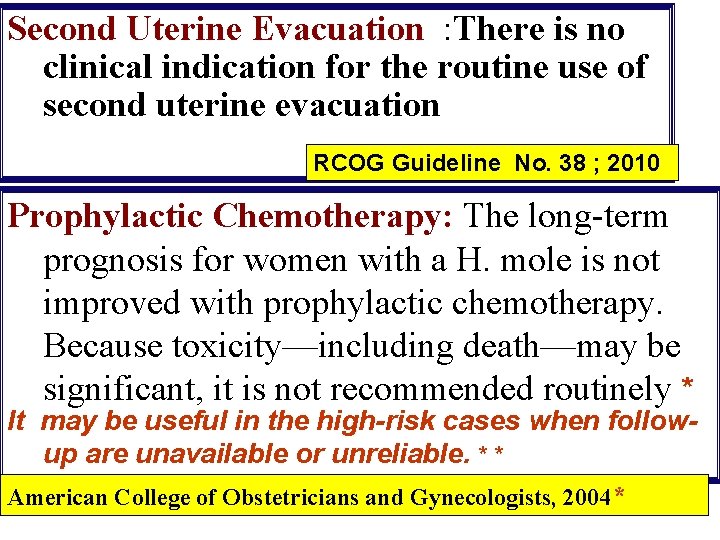

Second Uterine Evacuation : There is no clinical indication for the routine use of second uterine evacuation RCOG Guideline No. 38 ; 2010 Prophylactic Chemotherapy: The long-term prognosis for women with a H. mole is not improved with prophylactic chemotherapy. Because toxicity—including death—may be significant, it is not recommended routinely * It may be useful in the high-risk cases when followup are unavailable or unreliable. * * American College of Obstetricians and Gynecologists, 2004*